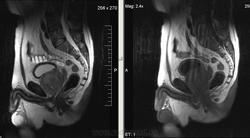

Метастазы рака простаты, кроме измений в позвонках видна сама первичная опухоль и лимфатические узлы (общий и наружный подвздошные слева, ещё один в левой подвздошной ямке).

После добавления томограмм исследования органов малого таза картина стала ещё печальнее...

Да, запустил пациент. До этого были проблемы с мочеиспусканием, рези, болезненность. Лечился самостоятельно от простатита, отмечал временное улучшение.